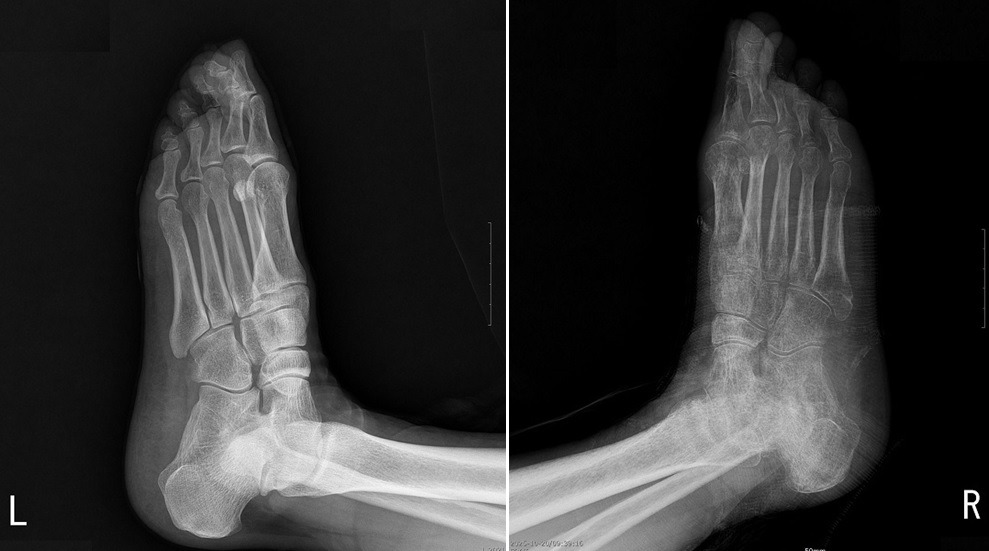

(*사진 설명 -> 우측 새끼 발가락 골절로 개인 의원에서 3개월간 부목고정으로 골절은 치유되었으나, '체중부하운동'이 전혀 안된 53세 여성으로 좌측 발 X-선 사진에 비해 우측 발 사진은 피질골이 얇아지고 골밀도가 현저히 감소된 심한 골다공증 소견을 보이고 있다. 장기간 사용하지 않아 뼈가 약해진 것이다.)